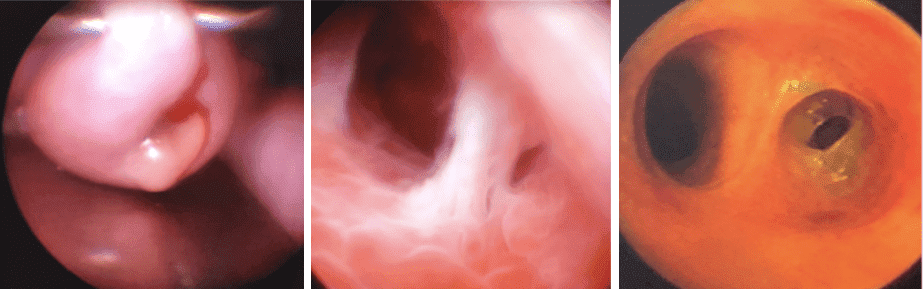

La histeroscopia es la técnica que permite observar directamente el interior del útero o matriz. Para ello, debe introducirse un endoscopio de pequeño calibre (3-5 mm) a través del orificio del cuello uterino y distender la cavidad.

Esto se consigue inyectando gas (CO2) o líquido (suero fisiológico) a bajas presiones a medida que penetra en el interior del útero, de modo que éste mantiene separadas sus paredes a lo largo de la exploración, permitiendo una nítida visión de su contenido, puede ser un procedimiento de consultorio o quirúrgico que requiera anestesia.

• Cuando la ecografía revela anomalías del interior del útero. (Miomas submucoso, pólipos, adherencias endometriales, DIU traslocado, algunas malformaciones como septos).